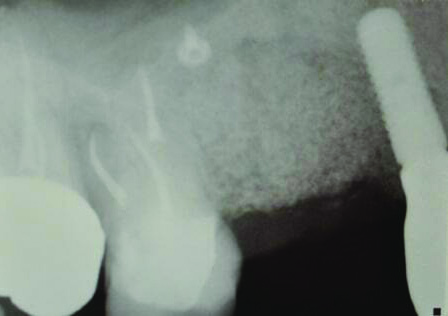

Fig 1 and Fig 2. Case 1: Initial clinical presentation with gutta-percha placed in the apical fistula of tooth No. 9 (Fig 1); radiograph showing gutta-percha point leading to the periapical lesion (Fig 2).

Patient 1: A 30-year-old female patient with an unremarkable medical history presented with implant No. 9 exhibiting retrograde peri-implantitis. Tooth No. 9 had been replaced with the implant 8 years prior because of a history of trauma and failed root canal treatment. The implant exhibited a periapical radiolucency with the sinus tract tracing to the apex of implant No. 9 (Figure 1 and Figure 2). The patient had a high smile line with longer clinical crowns at Nos. 9 and 10 compared with Nos. 7 and 8 (Figure 1 and Figure 2).